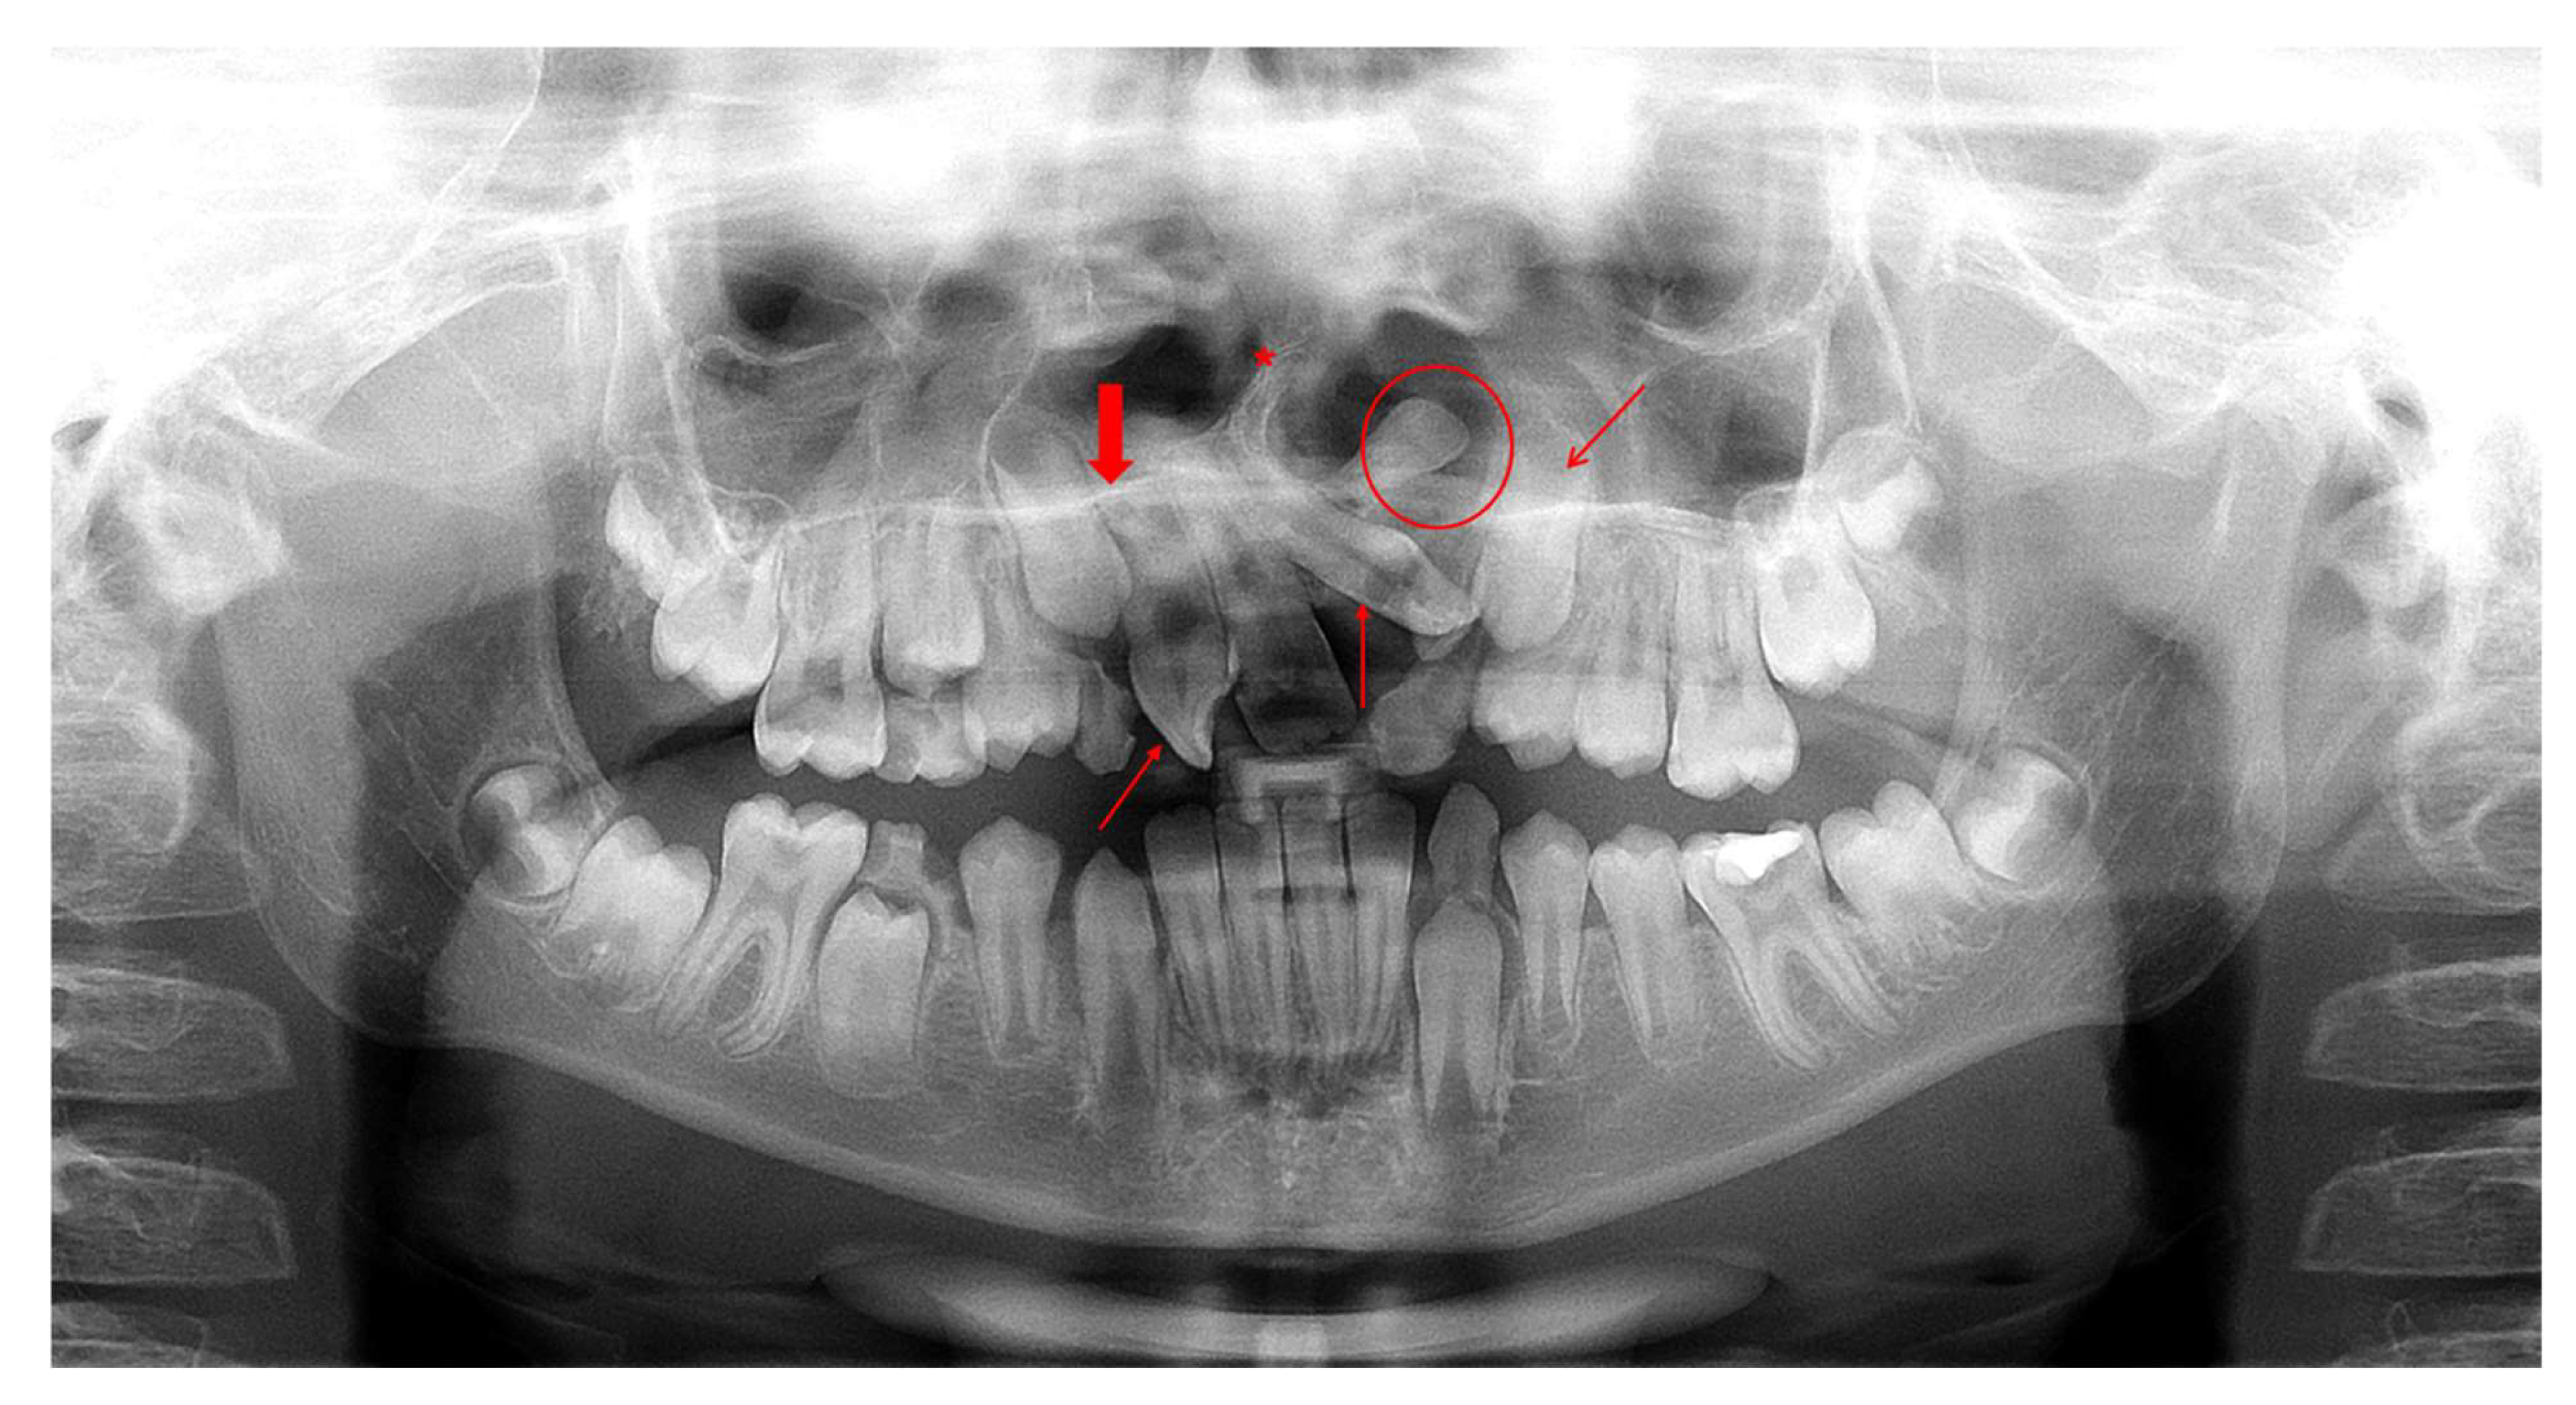

74.17% of the total sample presented IFs (Table 2). More specifically, the prevalence of IFs was 97.5% in the case group and 62.5% in the control group (Table 2). According to the Chi-square test, the higher prevalence of IFs that was reported in the case group compared with the control group was statistically significant [χ2 = 17.05, degrees of freedom (df) = 1, p <0.001, Table 3]. Representative radiographic images of CL/P patients are depicted in Figure 1, Figure 2 and Figure 3.

Figure 2. Imaging records of a male patient (10.7 years old) diagnosed with CP—UR presenting various incidental findings: (a) OPT indicates agenesis of teeth 12, 22 and 25 (bold red arrows), impaction of tooth 13 (thin diagonal red arrow), taurodontism of teeth 16, 26, 36 and 46 (thin horizontal red arrows) and deviated nasal septum to the right (red asterisk). (b) Cone-beam computed tomography (CBCT) image of two incidentally detected tonsilloliths (axial view; red arrows). R: right, L: left.